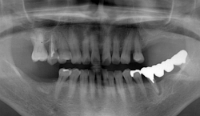

インプラントは、あごの骨に人工の歯の根(フィクスチャー・チタン製など)を埋め込み、その上に人工の歯を固定する、歯科の最先端医療技術です。当院では、最新のCT機械を導入し、以前にも増して、より精度の高い診断が可能となります。